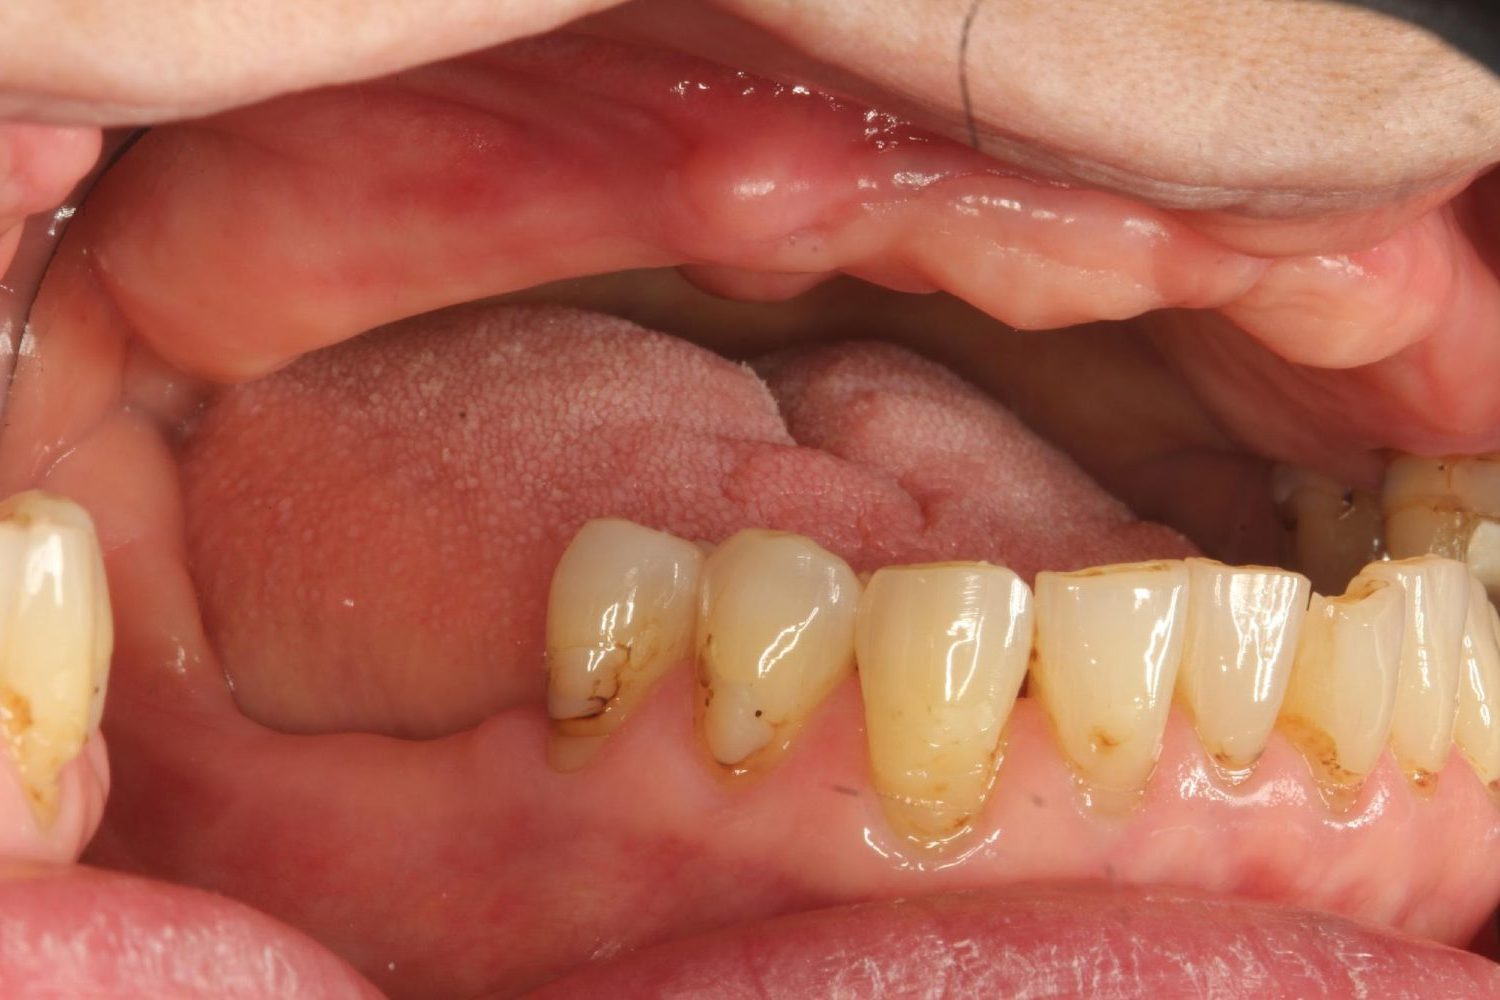

インプラント治療の症例紹介③

Before

After

主訴

むし歯の治療

治療内容

保存不可能な歯の抜歯

下顎にインプラント埋入し咬合再構成

治療費

2,688,400円(税込)

治療期間

14か月

治療回数

21回

想定されたリスク

※上部構造の形態が複雑になるため清掃が難しくなる。インプラント周囲炎の恐れがありました。

多数歯う蝕および多数歯欠損による咬合崩壊、保存不可能な歯の抜歯により上下無歯顎に。下顎に6本インプラント埋入する事で咬合再構成を行った。